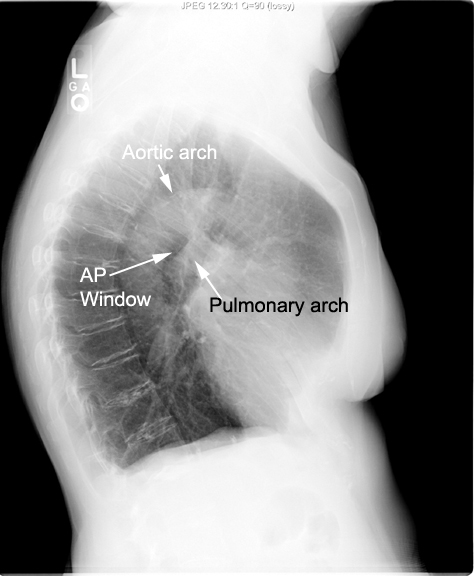

- Inferiorly

- Bifurcation of the pulmonary artery

- The left main bronchus